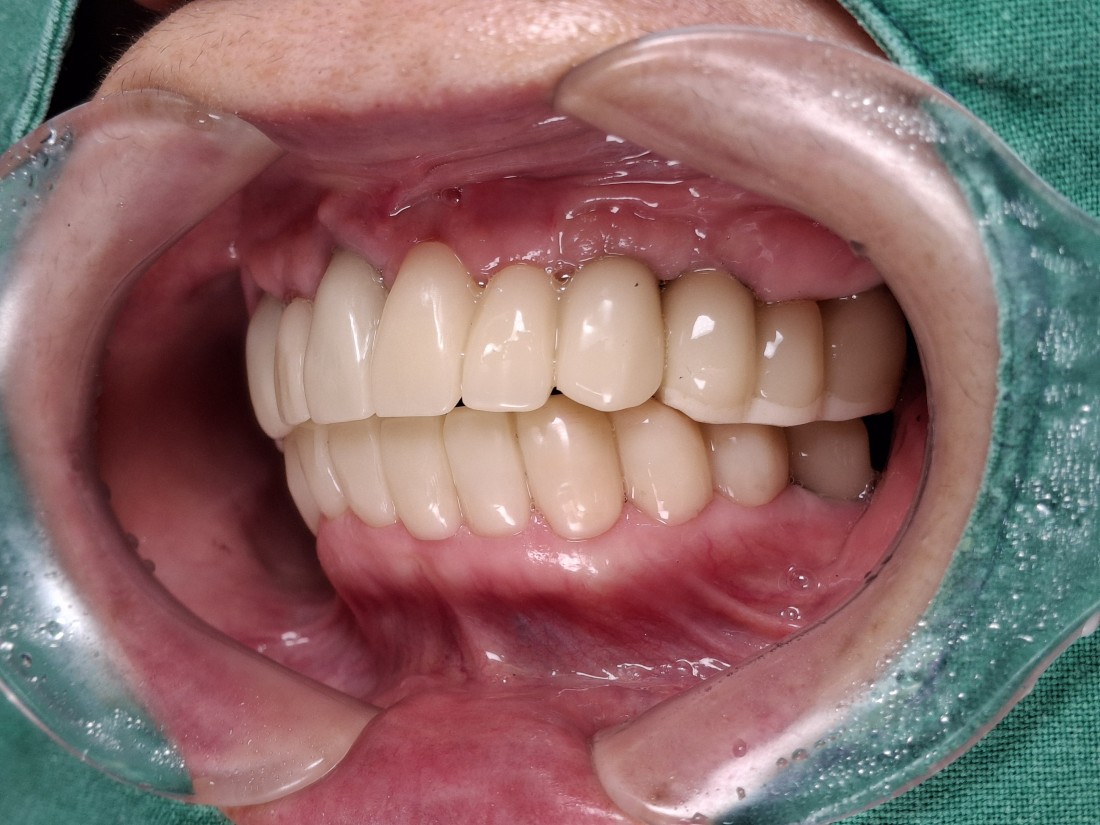

광주 상악임플란트를 해야하는 때가 오면

무엇보다도 '예쁘고 잘 씹어지게'

임플란트 진료를 받고싶으실텐데요.

광주 상악임플란트 치과는

4층 자체 치아기공소를 운영하고 있으며

보철물 디자인 퀄리티를

굉장히 중요하게 생각하고 진료하기 때문에

자연치아만큼 예쁘면서도

잘 씹어지는 광주 상악임플란트 진료를

보장할 수 있습니다.

만약 불편한 점이 생기셔도

자체 치아기공소에 바로 수정이 가능하여

빠르고 예쁘게, 잘 씹어지는

광주 상악임플란트를

완성하고 있습니다.